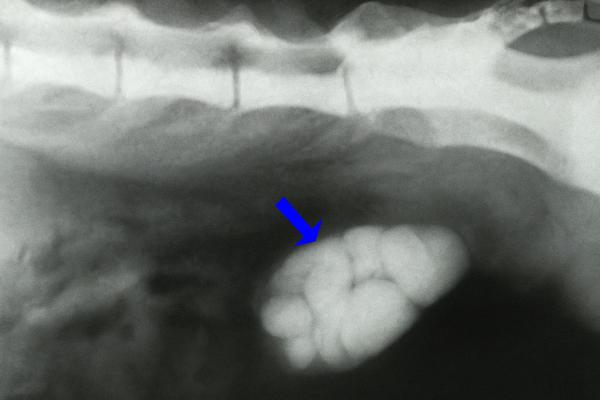

3. Cálculos

Los cálculos urinarios son masas sólidas formadas por minerales que se originan cuando ciertos compuestos químicos del organismo se cristalizan y se unen, principalmente en los riñones o en la vejiga urinaria. Estos cálculos pueden provocar hematuria en los perros debido a la irritación y el daño que producen en las paredes del tracto urinario, causando hemorragias.

Los cálculos pueden ser pequeños o de mayor tamaño, llegando incluso a obstruir el flujo de la orina, además de provocar dolor, dificultad al orinar e incluso predisponer a infecciones.

Los principales tipos de cálculos urinarios en perros son:

- Cálculos de estruvita: comunes en perros con infecciones urinarias por bacterias que descomponen la urea de la orina mediante la enzima ureasa, aumentando el pH y favoreciendo la formación de cristales de estruvita.

- Cálculos de oxalato cálcico: formados por cristales de oxalato de calcio; son duros y pueden causar dolor e incluso obstrucción urinaria. Suelen deberse a un exceso de calcio en la dieta o a enfermedades que provocan hipercalcemia.

- Cálculos de urato: constituidos por ácido úrico, relacionados con una alteración en el metabolismo de las purinas presentes en las proteínas.

- Cálculos de cistina: se producen en perros con predisposición genética a excretar una cantidad excesiva de cistina en la orina.

- Cálculos mixtos: aparecen cuando un mismo perro presenta más de un tipo de cálculo, por ejemplo, de oxalato cálcico y estruvita.

Tratamiento

Ante un perro con cálculos urinarios, lo primero es determinar el tipo, tamaño, ubicación y el grado de daño que producen. Algunos cálculos, como los de estruvita, pueden disolverse mediante dietas específicas o cambios en la alimentación, mientras que los de oxalato cálcico requieren tratamiento quirúrgico.